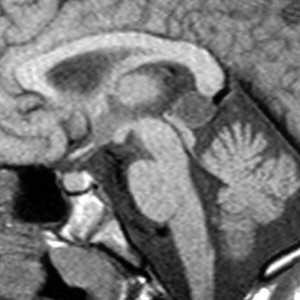

Пинеальная киста расположена в проекции шишковидной железы. Встречается с частотой 4-11%. Размеры обычно не превышают 1 см, но изредка встречаются больших размеров. В таких случаях она вызывает окклюзионную гидроцефалию. При головного мозга она имеет все признаки кисты с примесью белка в жидкости, то есть немного светлая на Т1-взвешенных. Изредка встречается геморрагическое содержимое. Киста может контрастироваться по периферии.

![gpineal_cyst_fig1a]()

МРТ головного мозга. Сагиттальная Т1-взвешенная МРТ. Пинеальная киста.

Пинеальная киста расположена в проекции шишковидной железы. Встречается с частотой 4-11%. Размеры обычно не превышают 1 см, но изредка встречаются больших размеров. В таких случаях она вызывает окклюзионную гидроцефалию. При МРТ головного мозга она имеет все признаки кисты с примесью белка в жидкости, то есть немного светлая на Т1-зависимых МРТ. Изредка встречается геморрагическое содержимое. Киста может по усиливаться периферии при МРТ головного мозга с контрастированием.

![Pineal cyst]()

МРТ головного мозга. Т1-взвешенная сагиттальная МРТ. Пинеальная киста.